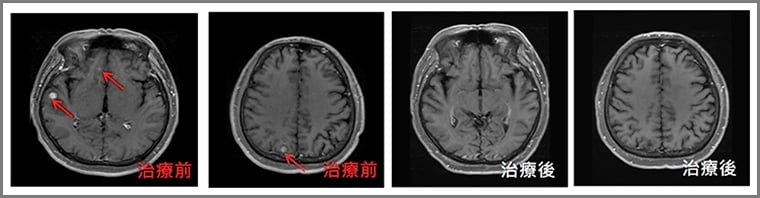

近年來,由於放射治療的進步,醫師可以在全腦放射治療時,盡量避開海馬迴的範圍,以減少病人後續記憶力減退的情形,也就是透過電腦的精準運算,調整放射線的分布,可以降低海馬迴接受的放射劑量,達到打擊腦腫瘤同時,又保護記憶認知功能的雙贏效果。

根據最新臨床腫瘤學期刊的研究,針對腦部轉移且身體狀況良好的病人,使用閃避海馬迴全腦放射治療,可以在不影響腫瘤控制效果的情況下,減少病人記憶與學習功能退化的程度。精準醫療已可讓這類病人避開海馬迴腦的照射,治療後仍保有不錯的記憶,活得也有尊嚴。

奇美醫院放射腫瘤部主治醫師林佳輝指出,去(112)年奇美醫院放射腫瘤部已有23位病人選擇閃避海馬迴全腦放射治療。根據病人及家人的觀察,病人與治療前相比並沒有記憶力退化的現象,且經過臨床醫師的觀察,記憶、學習、空間感與認知功能皆維持與治療前相當。